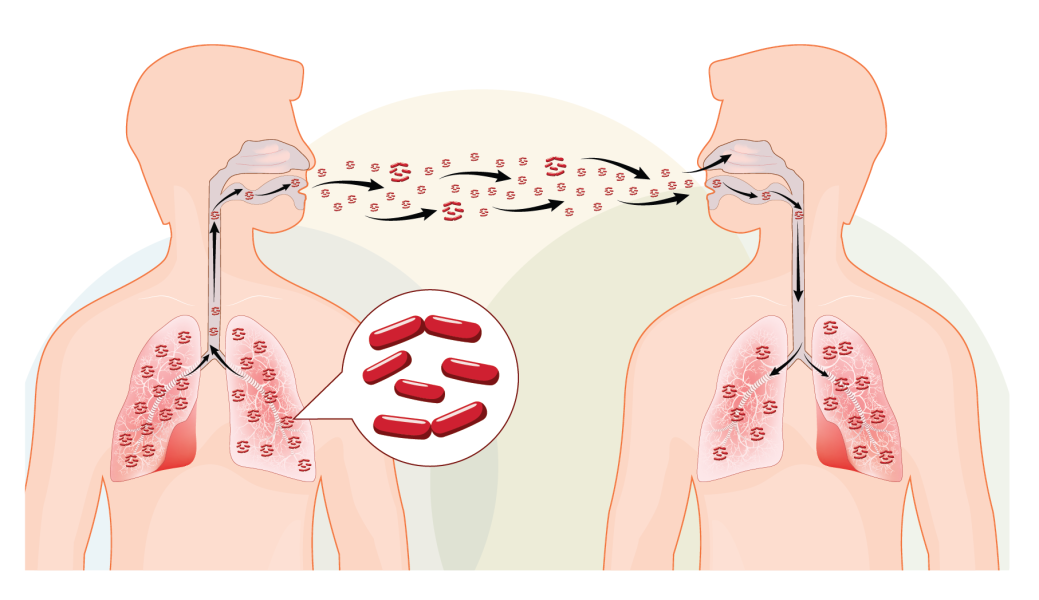

Tuberculosis (TB)

Jaipur sees many TB cases each year. We offer reliable testing and DOTS-based treatment

plans for tuberculosis, including drug-resistant TB. Early diagnosis ensures fast recovery and

limits transmission.